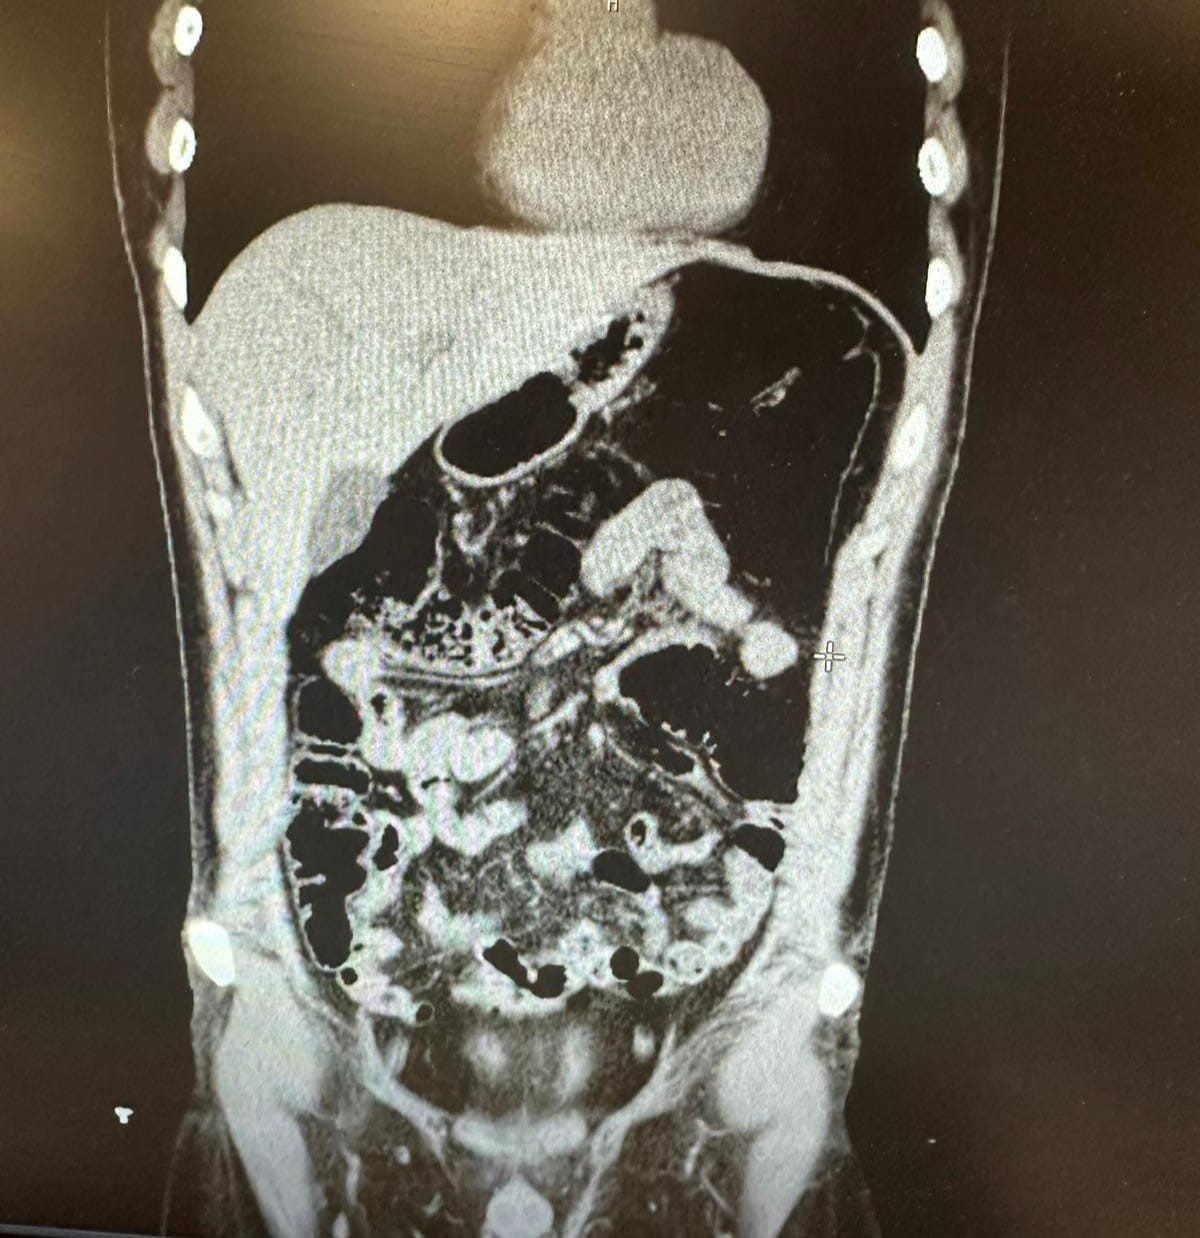

Ekiplerin yürüttüğü saha çalışmalarında uyuşturucu kuryeliği yapan İran uyruklu bir şahıs tespit edildi. Polis, şüphelinin Konya’da gizlendiği adresi tespit ederek operasyon düzenledi. Şüpheli ve beraberindeki 4 kişi gözaltına alındı. Şüpheli, uyuşturucu yuttuğunu ifade etmesi üzerine hastaneye kaldırıldı. Şüpheli, 2 gün boyunca polis nezaretinde hastanede gözlem altında tutularak midesinde kapsüller halinde bulunan eroin maddesi doğal yollarla dışarı çıkarıldı. Şüphelinin ifadesinde para karşılığında uyuşturucu sevkiyatı yapmasının istendiği ve kabul ettiği ortaya çıktı. Şüphelinin İran’da uyuşturucu maddeleri kapsüller halinde yuttuktan sonra yasal yollarla Türkiye’ye giriş yaptığı ve uyuşturucuyu piyasaya sürmek üzere taksiyle Konya’ya geldiği öğrenildi. Ayrıca; şahsın İran’da bilinen bir iş adamı olduğu, şeker ve çay ticareti yapmak için sık sık Türkiye’ye giriş çıkış yaptığı anlaşıldı.

Konya’da konakladıkları evin tespit edilmesiyle 1’i İran uyruklu 5 şüpheli yakayı ele verdi. İran uyruklu V.F.G.’nin midesinde 300 gram, gizlendiği adreste Narkotik köpeği Alex ile yapılan aramada ise toplam 6 parça halinde 1 kilogram eroin, bir miktar metamfetamin ve bir miktar uyuşturucu hap ele geçirildi. V.F.G. ile birlikte gözaltına alınan ve uyuşturucu sevkiyatını organize ederek yardım ve yataklık yapan M.P., Ö.T., F.S. ve M.A. uyuşturucu madde ticareti yapmak ve uyuşturucu madde kullanmak suçlarından gözaltına alındı. Daha önce de birçok suç kaydı bulunan şüpheliler sevk edildiği adli makamlarca tutuklanarak cezaevine gönderildi. İHA